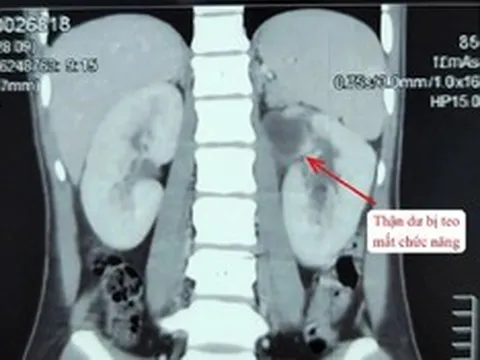

Vừa qua, Bệnh viện Từ Dũ (Tp.HCM) cho biết vừa phẫu thuật thành công cho nữ bệnh nhân 25 tuổi có khối u xơ tử cung nặng gần 12 kg, được xem là lớn nhất từ trước đến nay tại bệnh viện. Đáng chú ý, ê-kíp đã bảo tồn được tử cung, qua đó giữ lại cơ hội sinh sản cho bệnh nhân.

Đây là trường hợp bệnh lý phức tạp khi người bệnh không chỉ mang khối u xơ tử cung khổng lồ (tương đương 1 trường hợp song thai 36 - 38 tuần) mà còn đối mặt với nguy cơ thuyên tắc phổi và tai biến tim mạch rất cao trong thời gian phẫu thuật.

Ê-kíp phẫu thuật đối mặt với việc khối u dính chặt vào phúc mạc, mạc nối và các quai ruột non. Hệ thống mạch máu nuôi u tăng sinh mạnh mẽ với những mạch máu có đường kính lên tới 7 mm.